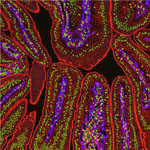

Credit: Chris McCulloh.